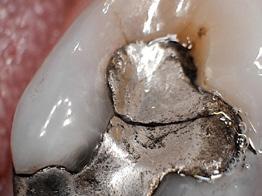

Today, approximately 40% to 50% of dental offices use digital intraoral scanning, and this percentage is only expected to grow.1 Current systems include a scanner with the head created to fit within the oral cavity to capture files of the entire dentition. The files can be used to create restorations as well as appliances either within the dental office or via a lab. While digital intraoral scanning once focused solely on restorative needs, the opportunities for its use have expanded to applications in orthodontics and pathologies such as caries, erosion, and oral cancer. In modern dental practices, this technology can also be integrated into the dental hygiene appointment.1-4

Dental hygienists independently utilize digital scanning for education and motivation. Not only can the clinician educate the patient with the images, but the patient has a visual that is easily understood. These images contain powerful visuals of attrition, fractured teeth, abfraction, gingival recession, overjet, and crowding.4 Biofilm can be displayed after the application of disclosing solution.5 Separate photos are not required to capture the biofilm present when using digital scanning.